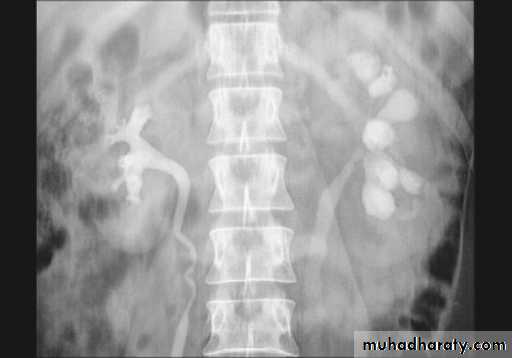

A. First a plain x-ray of the abdomen is taken before the injection of the contrast media, also known as A KUB (kidney, Ureter and Bladder). Calcification & stones may be obscured & missed by contrast media if plain film not takenfirst .B. Films taken after injection of contrast’ medium:

1.Nephrogram phase (Immediately after injection of contrast) .

2. Pyelogram Phase(l-5 minutes after injection of contrast) .3. After 10 minutes with compression, to get better distention of the pelvis and calyces.

4. Full length film after release of compression .

Interpretation of IVU films (what to look for?):

The kidneys:Check their position (left kidney is usually higher).

Identify the whole of both renal outlines, look for any indentations or bulges:

Renal parenchymal width should be uniform(2-2.5cm)

measure renal lengths:

Normal length of adult kidney at IVU is 10-16cm. This is higher than in ultrasound due to image magnification.